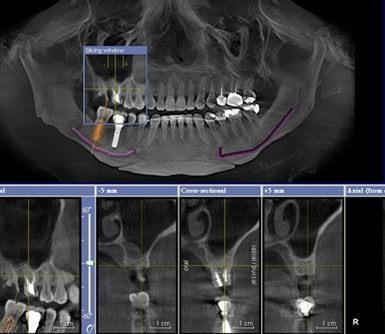

2、CT片:也叫CBCT,相對於(yu) 全景片來說,是從(cong) 三維的角度查看牙齒情況的,可以了解牙齒更細微、更為(wei) 全麵的一些情況。價(jia) 格通常要比其他牙片都貴一些,在三四百元左右。如下圖:

CT片